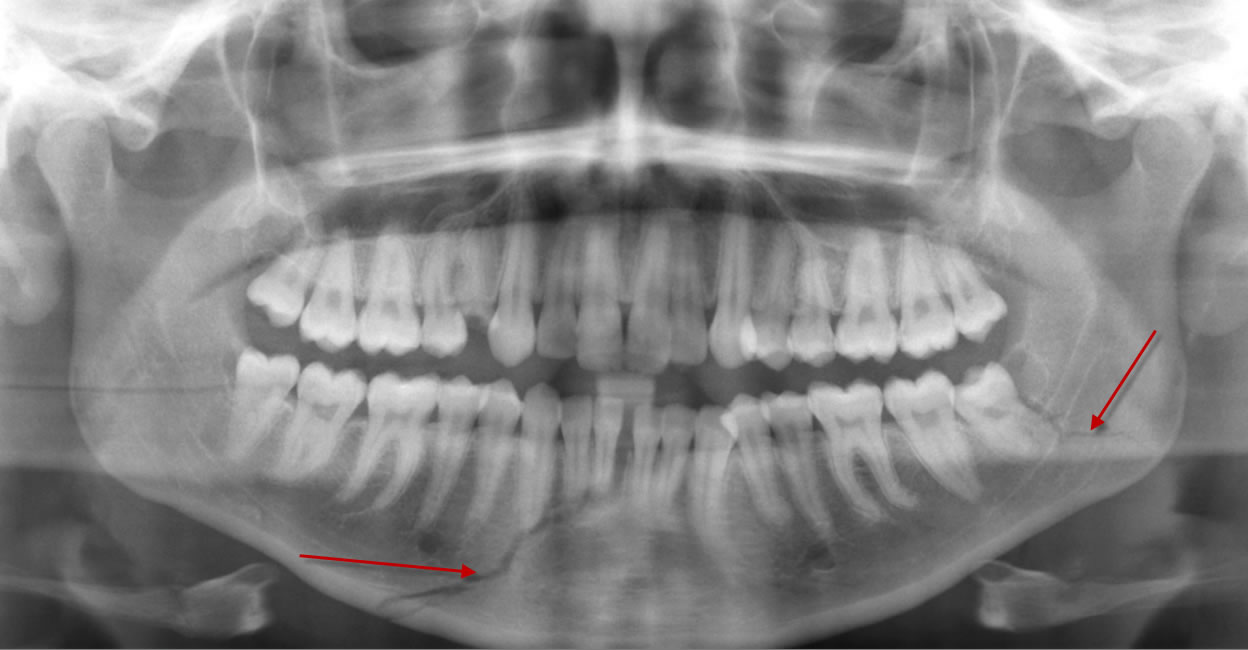

• Рентгенография. В случае травм челюсти, остеомиелита делают снимки нижней челюсти. При подозрении на травму позвоночника проводится рентгенография шейного отдела позвоночника.